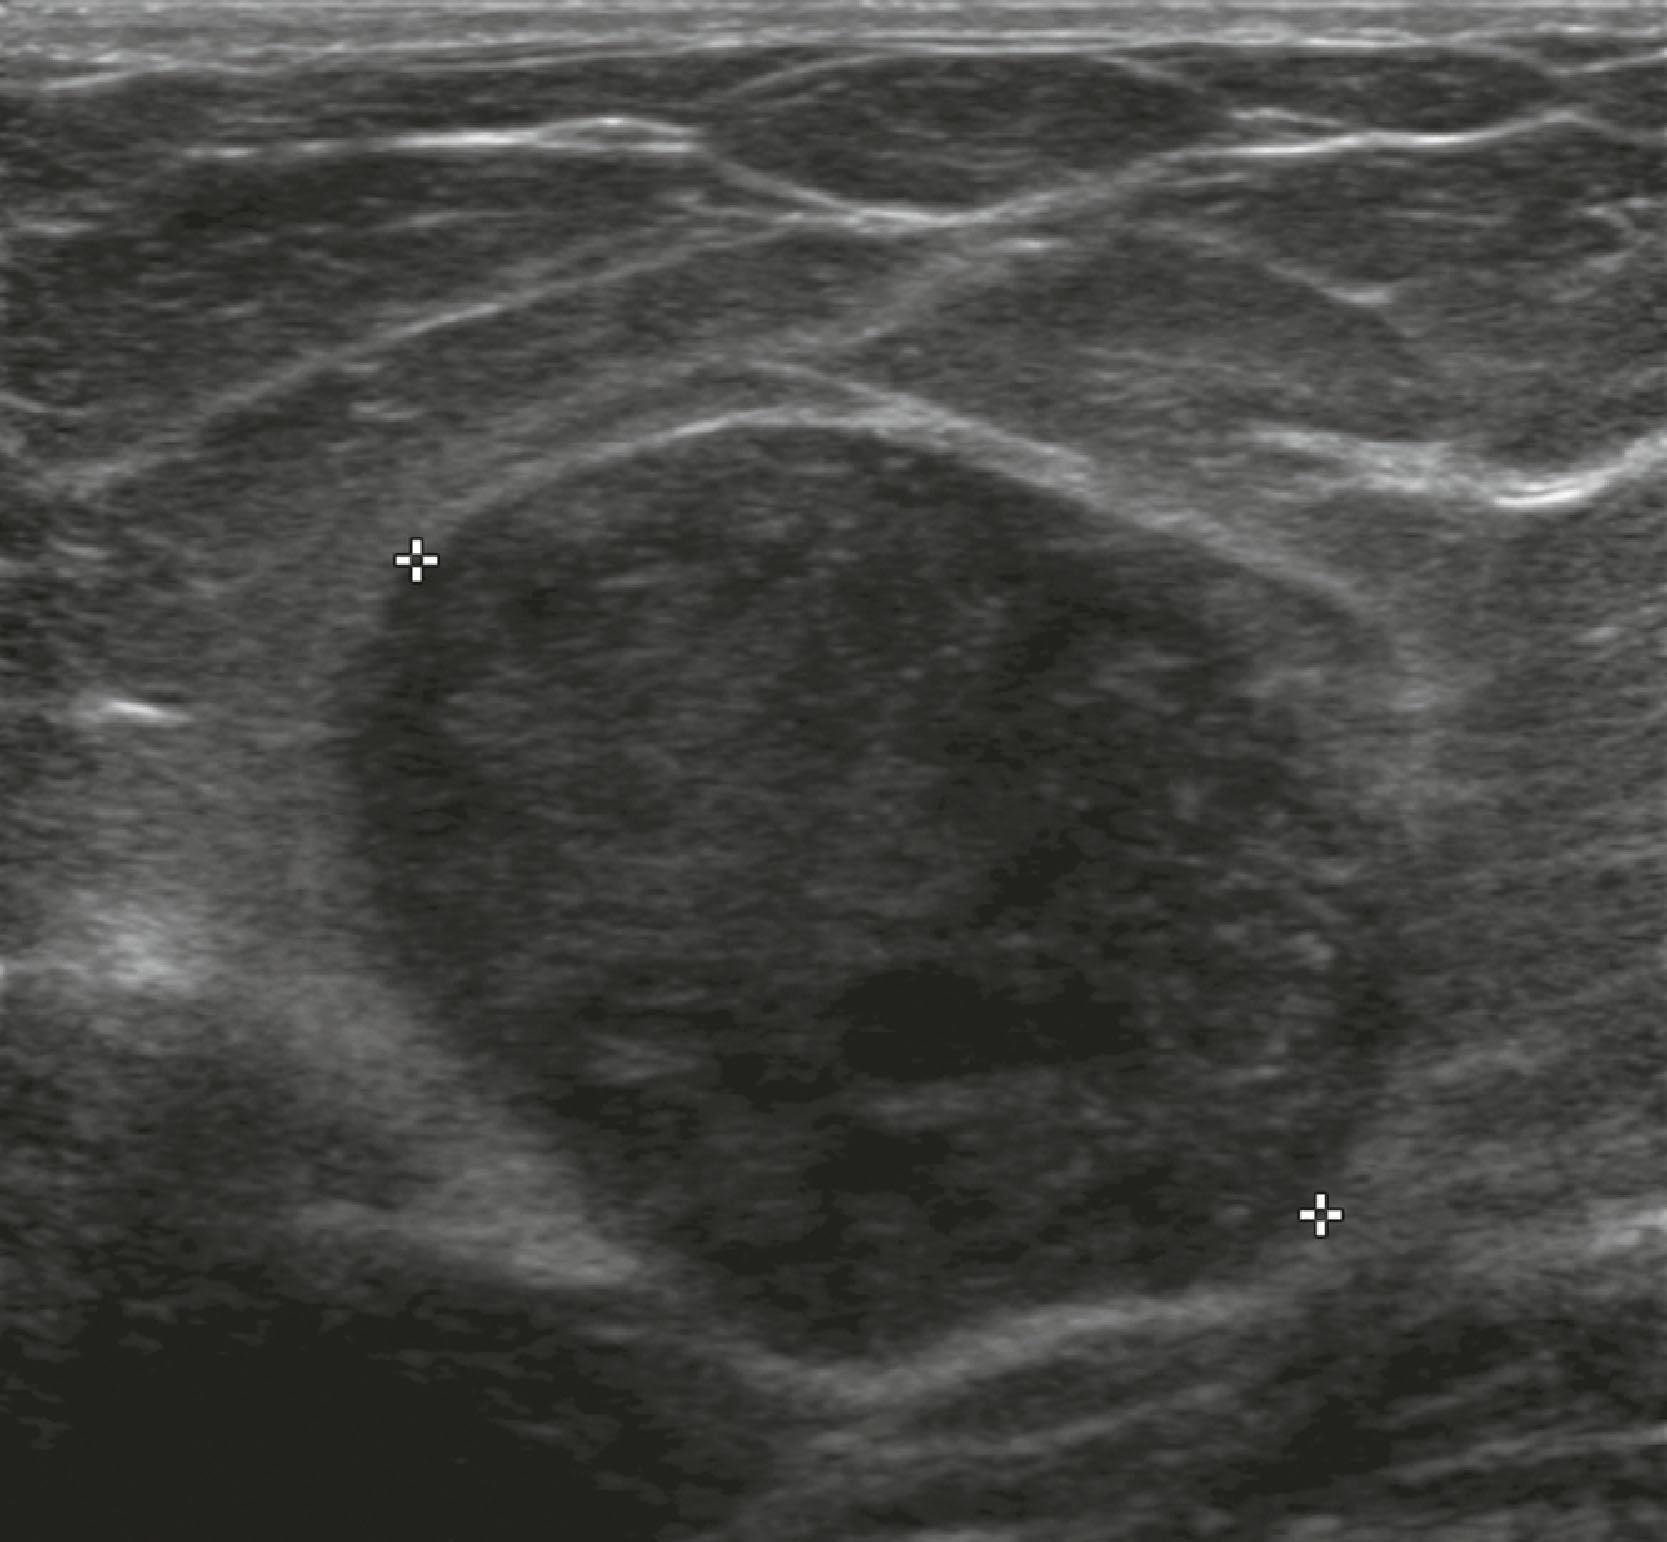

Sonographic features of benign masses, originally reported by Stavros and coworkers, include three or fewer gentle lobulations, orientation parallel to the chest wall, and a thin echogenic pseudocapsule, along with absence of any malignant features. Other features favoring a benign etiology are oval shape, circumscribed borders, and uniform hyperechogenicity ( Fig. 8.15 ). However, many benign-appearing masses undergo percutaneous or excisional biopsy because they are new or enlarging and cannot be unequivocally distinguished from well-circumscribed malignancies ( Fig. 8.16 ). A very large but well-defined mass is suspect for a phyllodes tumor ( Fig. 8.17 ).

Fig. 8.16, This 4.5-cm palpable mass has well-defined margins on Right Mediolateral Oblique view (RMLO) on mammography ( A ), but on sonography ( B ), it has inhomogeneous internal echoes and a few microlobulations. Biopsy revealed infiltrating duct carcinoma, nuclear grade 3.

Fig. 8.17, This 3.4-cm palpable malignant phyllodes tumor has circumscribed margins. Pathology revealed mild to moderate pleomorphism, with six mitoses per 10 high-power fields.